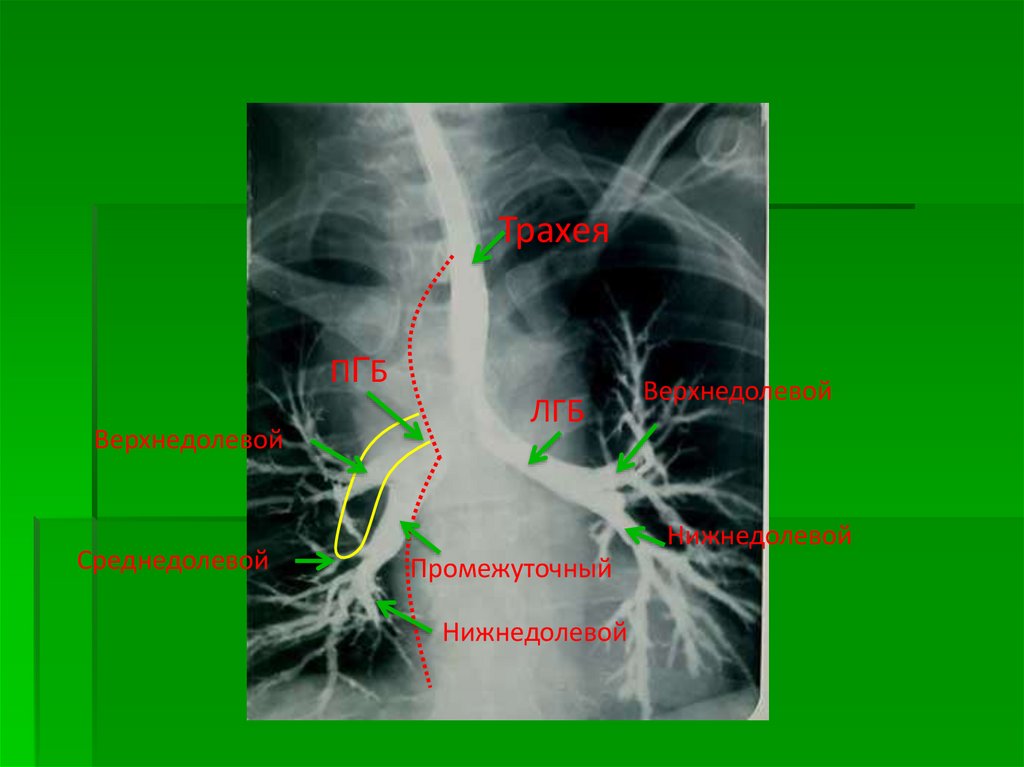

6.

Трахея

ПГБ

Верхнедолевой

Среднедолевой

ЛГБ

Нижнедолевой

Промежуточный

Схема расположения камер сердца и

крупных сосудов при контрастном

исследовании

1 — трахея, 2 — правый главный бронх, 3

— правый верхнедолевой бронх, 4 —

верхняя полая вена, 5 — ортопроекция

артерии правого III сегмента, 6 — правая

верхнедолевая вена, 7 — нисходящая

ветвь правой легочной артерии, 8 —

правая базальная вена (из нижней

группы легочных вен), 9 — контур

диафрагмы справа, 10 — дуга аорты, 11

— ортоградная проекция левой легочной

артерии, 12 — артерия III левого

легочного сегмента, 13 — левая

верхнедолевая вена, 14 — левая

нижнедолевая вена, 15 — легочный

ствол, 16 — левое предсердие, 17 —

левый желудочек, 18 — левый

верхнедолевой бронх, 19 — правая

легочная артерия, 20 — левый главный

бронх.